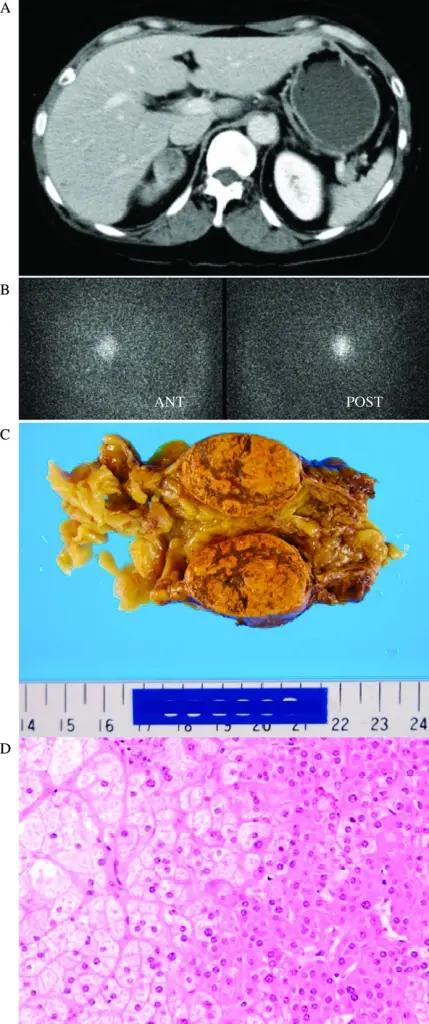

Pheochromocytoma

A particular kind of neuroendocrine tumor (NET) known as a pheochromocytoma develops from chromaffin cells.

Chromaffin cells are located in the adrenal glands and create hormones that the body requires.

Clinical features of pheochromocytoma results from elevated serum catecholamine levels.

Clinical features of pheochromocytoma include:

- Perspiration

- Tachycardia

- Palpitations

- Headaches

- Episodic hypertension

Increased 24-hour urine production and serum metanephrine levels are used to diagnose the disease.

Medical excision is used as a treatment of choice.

When the tumor is manipulated, catecholamines may leak into the bloodstream.

An irreversible alpha-blocker called phenylbenzylamine is given preoperatively to stop a hypertensive crisis.

Pheochromcytomas often follows the rule of 10s:

- 10% bilateral

- 10% familial

- 10% malignant

- 10% located outside of the adrenal medulla such as bladder wall or organ of Zuckerkandl at the inferior mesenteric artery root